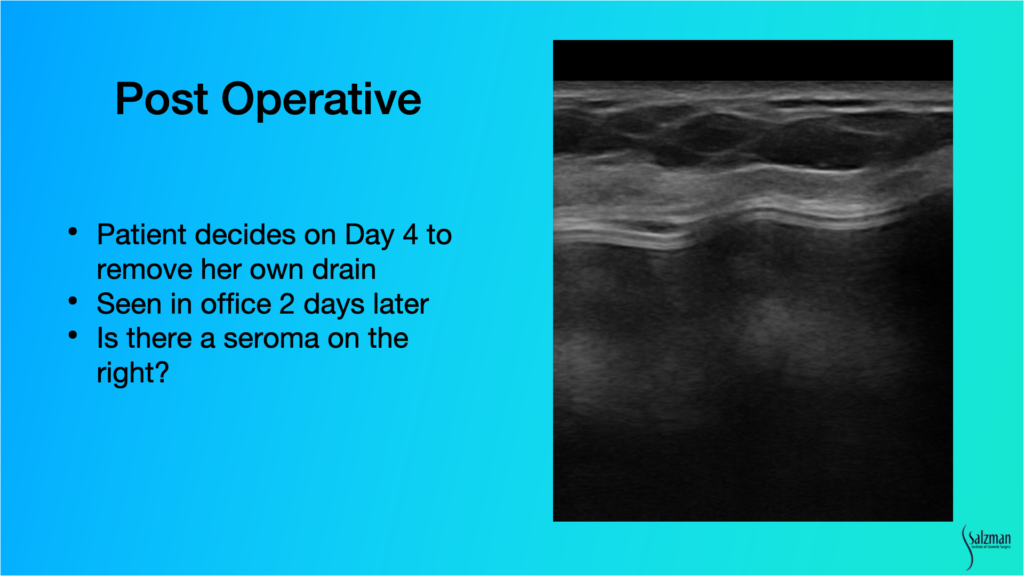

Patient Causes Post-Operative Complication

The only time I ever use drains for breast surgery is when I put in Strattice or I do a capsulectomy. So, in this case, I put a drain in. On day four the patient decided to remove her own drain. When she came to the office two days later, I was concerned she may have caused a seroma. With ultrasound, I was able to see a little tiny bit of fluid, which I decided to watch. I examined her again with ultrasound about a week later, and the fluid had been reabsorbed.

If I didn’t have ultrasound, I would have sent her to a radiologist for another $1,500 exam and aspiration. He would say he’s afraid to put a needle in because it’s an implant. With ultrasound, I know that I can stick the seroma and not stick the implant. I can see it. It’s so easy.

In summary, high-resolution ultrasound allowed for an immediate, day of, consult diagnosis of both the seroma and broken implant. It led to a treatment plan that day. I scheduled an appropriate procedure and afterwards was able to use ultrasound to assess that when the patient decided to remove the drain, it was probably okay.